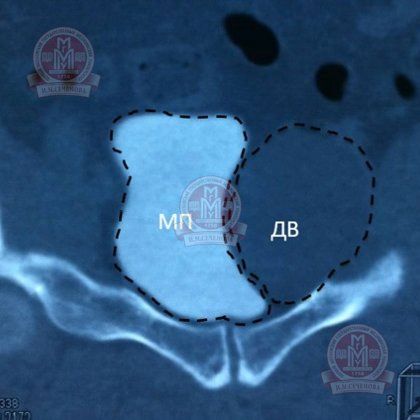

Малюнок №7 (МСКТ). Сечовий міхур (МП) в процесі дослідження заповнюється контрастною препаратом, створюється відчуття наявності зв'язку між сечовим міхуром і освітою (ДВ).

Малюнок №8 (МСКТ). Сечовий міхур (МП) заповнений контрастом, рідинне утворення (ДВ) не накопичує контраст.